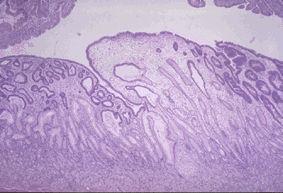

질환(병리주체)의 분류 종양양 병변/연소성 용종증

부위(장기별) 위(부위)/기타

검사방법 마이크로